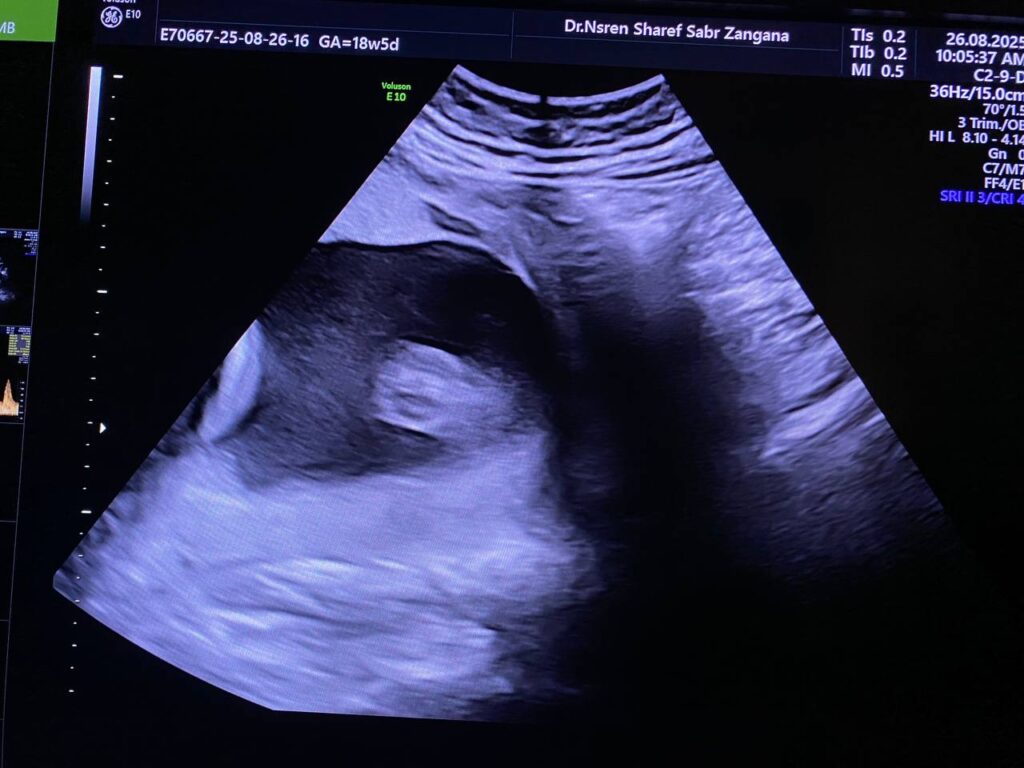

Multiple congenital anomaly seen , brain show hydrocephaly , lumbosacral myelomeningocele 18x19mm , both hips and femurs are abducted with flexed both legs , and both feet show rocking feet morphology , both hands are also fisted , mostly Arnold Chiari Malformation type 2 ?? or other congenital anomaly , for further study ( genetic study )

Normal in amount of liquor

F.L. = 18w+5d

B.P.D. = 19w+1d

Fetal body weight about =306gram, A.C = 40%